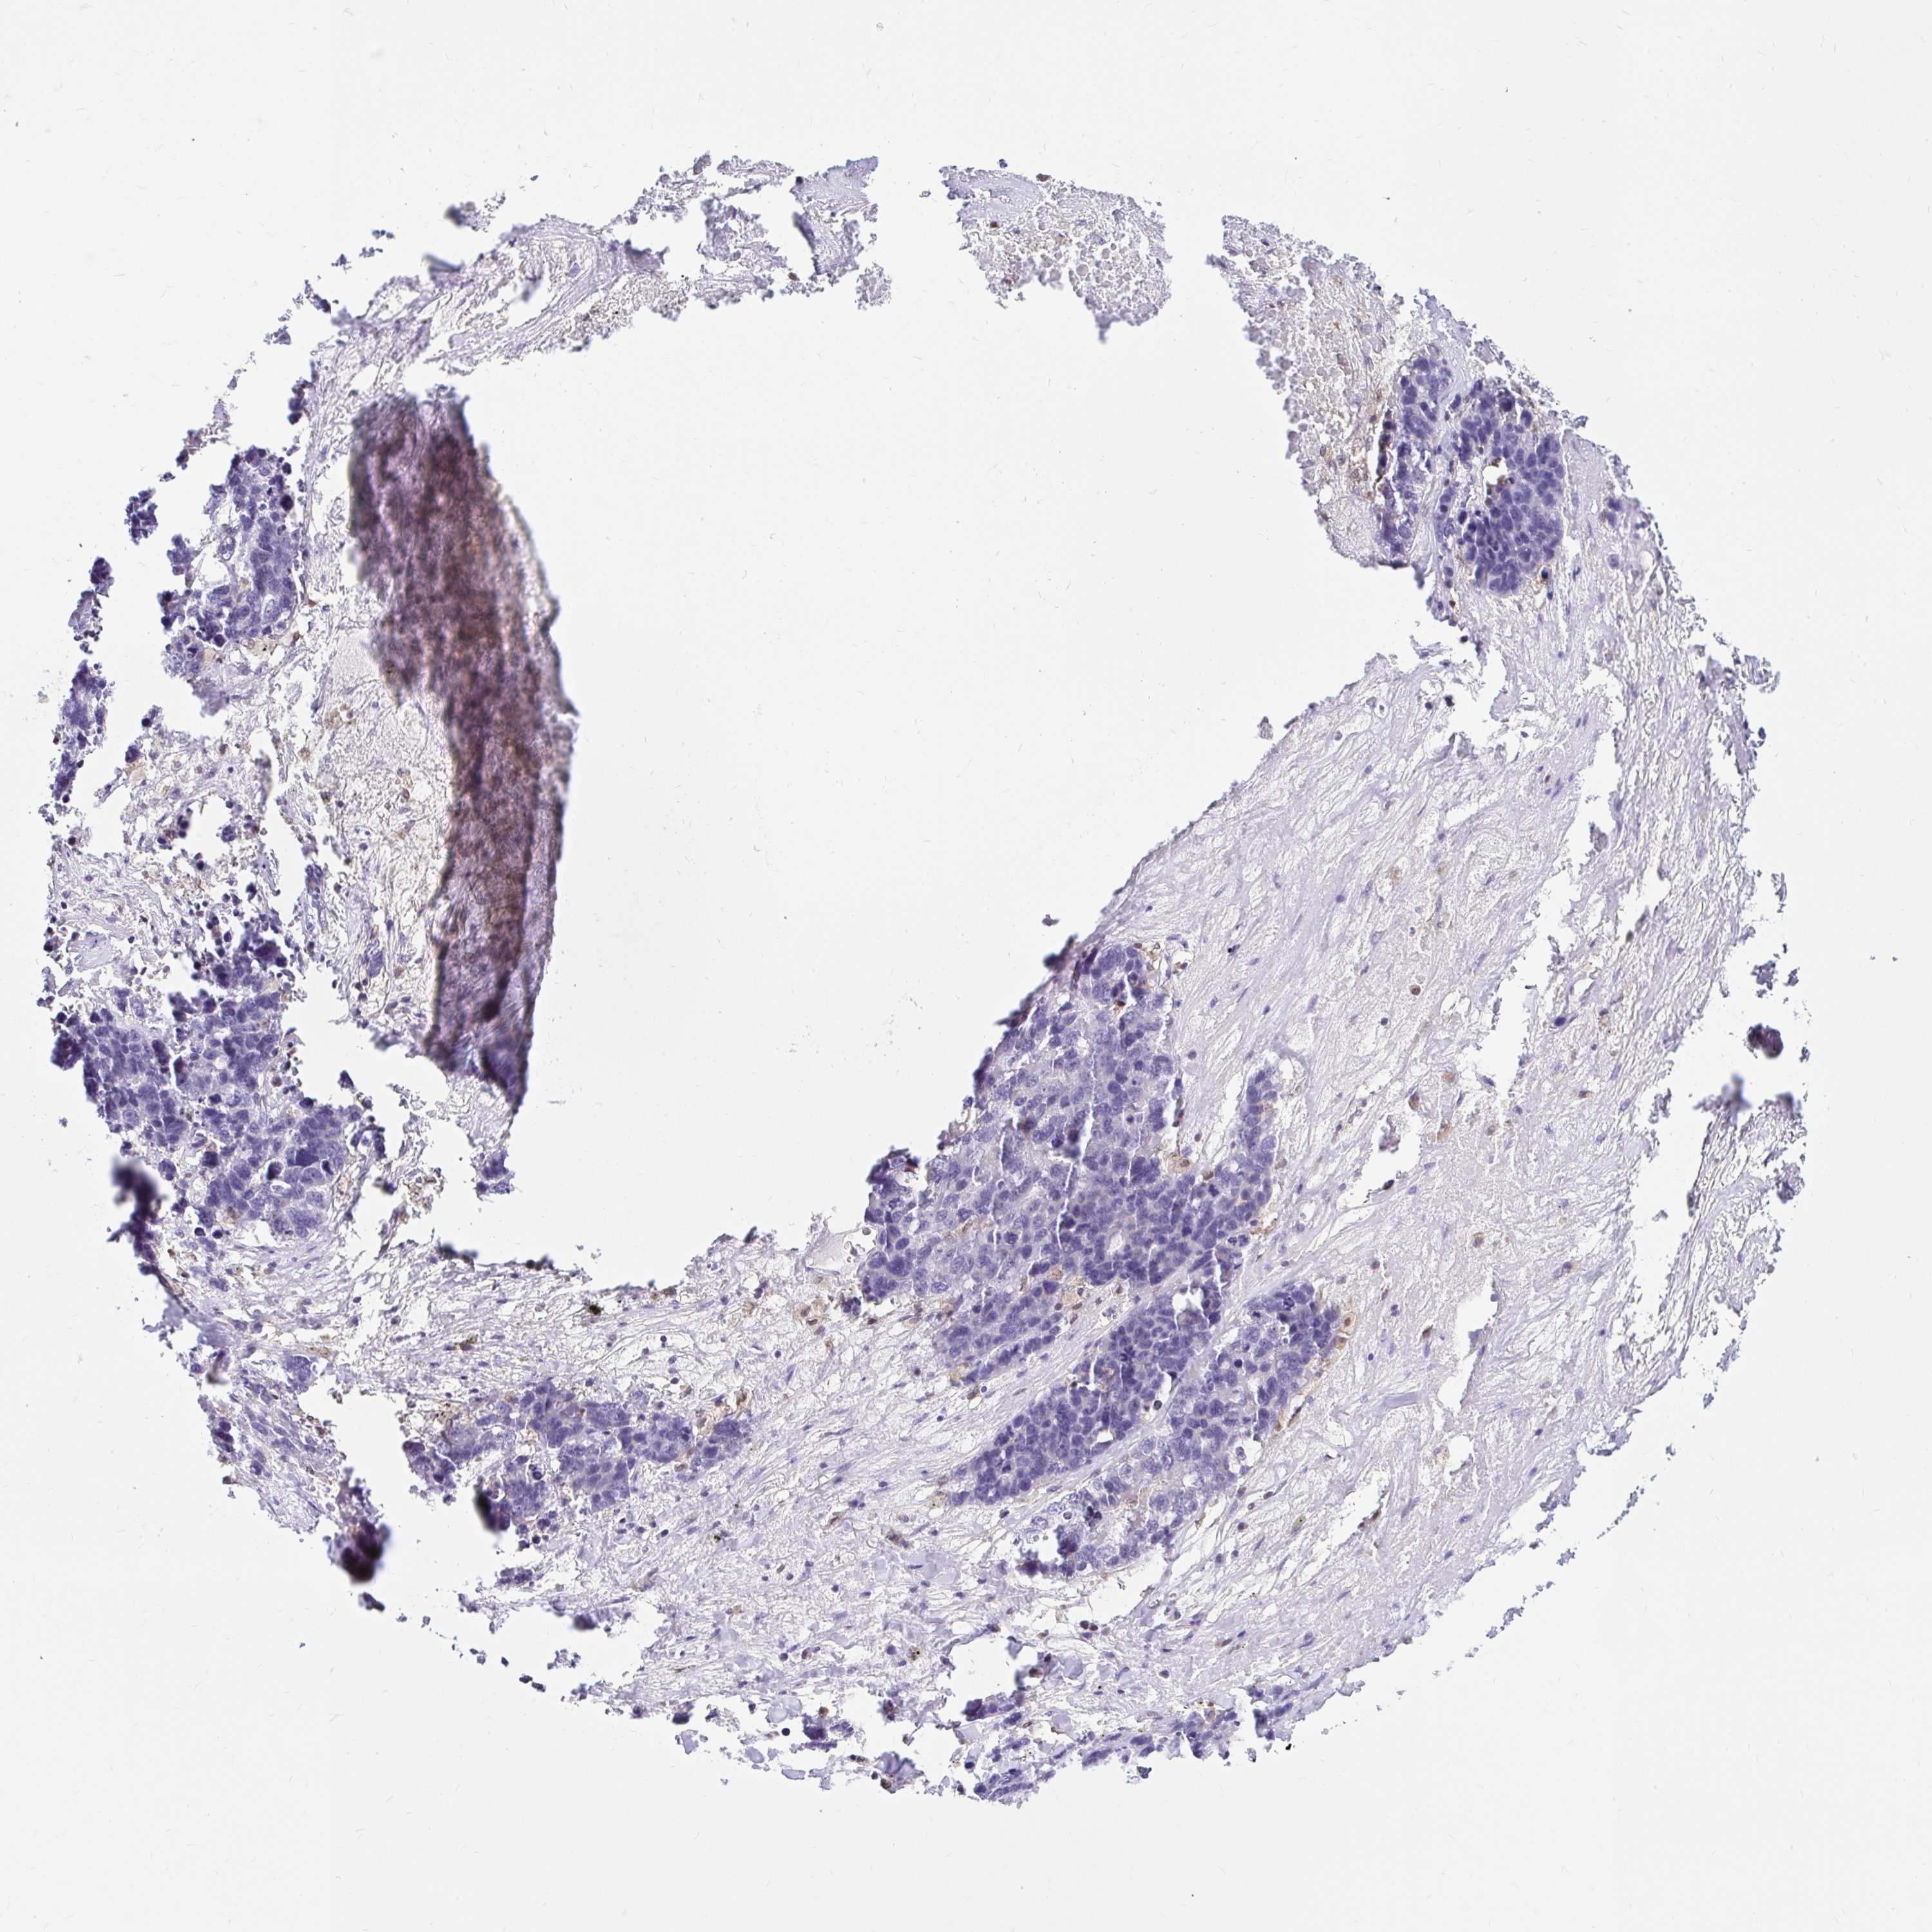

LUNG SQUAMOUS CELL CARCINOMA (TCGA) - Interactive survival scatter ploti

The Survival Scatter plot shows the clinical status (i.e. dead or alive) for all individuals in the patient cohort, based on the same data that underlies the corresponding Kaplan-Meier plots. Patients that are alive at last time for follow-up are shown in blue and patients who have died during the study are shown in red.

The x-axis shows the expression levels (FPKM) of the investigated gene in the tumor tissue at the time of diagnosis. The y-axis shows the follow-up time after diagnosis (years). Both axes are complimented with kernel density curves demonstrating the data density over the axes. The top density plot shows the expression levels (FPKM) distribution among dead (red) and alive patients (blue). The right density plot shows the data density of the survived years of dead patients with high and low expression levels respectively, stratified using the cutoff indicated by the vertical dashed line through the Survival Scatter plot. This cutoff is automatically defined based on the FPKM cutoff that minimizes the p-score. The cutoff can be changed by dragging the vertical line or by entering a cutoff value in the square labeled "Current cut-off".

Under the Survival Scatter plot the p-score landscape (black curve; left axis) is shown together with dead median separation (red curve; right axis). Dead median separation is the difference in median mRNA expression between patients who have died with high and low expression, respectively. It is calculated as follows: median FPKM expression of dead patients with high expression - median FPKM expression of dead patients with low expression. This is intended to aid the user in visually exploring custom cutoffs and the associated p-scores and dead median separation.

Individual patient data is displayed and can be filtered by clicking on one or more of the category buttons on the top of the page. Categories describing expression level and patient information include: high, low, alive, dead, female, male and tumor stages. The scale of the x-axis can be toggled between linear and log-scale by clicking on the "x log" button. Mouse-over function shows TCGA ID, patient information and mRNA expression (FPKM) for each patient.

& Survival analysisi

Kaplan-Meier plots summarize results from analysis of correlation between mRNA expression level and patient survival. Patients were divided based on level of expression into one of the two groups "low" (under cut off) or "high" (over cut off). X-axis shows time for survival (years) and y-axis shows the probability of survival, where 1.0 corresponds to 100 percent.

PYCARD is not prognostic in Lung Squamous Cell Carcinoma (TCGA)

: 53.54